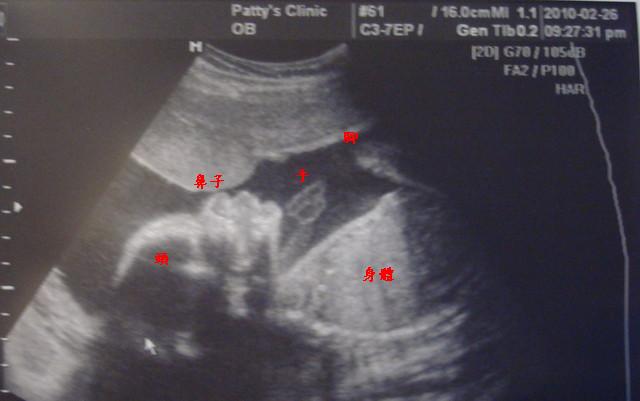

再加上我跟弟妹肚子裡各有一隻小老虎,